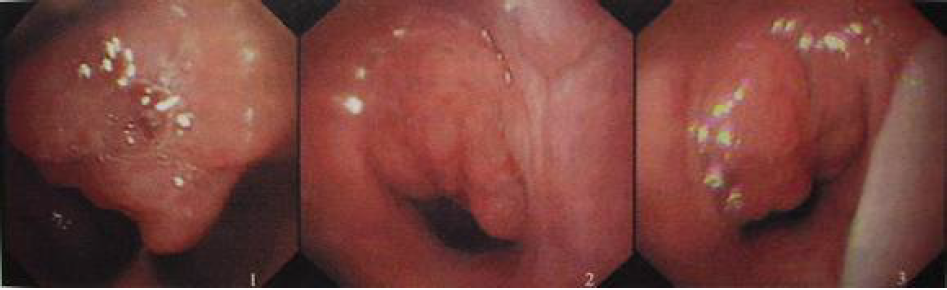

咽扁桃体又称腺样体或增殖腺,位于鼻咽部顶部与咽后壁处,属于淋巴组织

儿童鼾症腺样体肥大